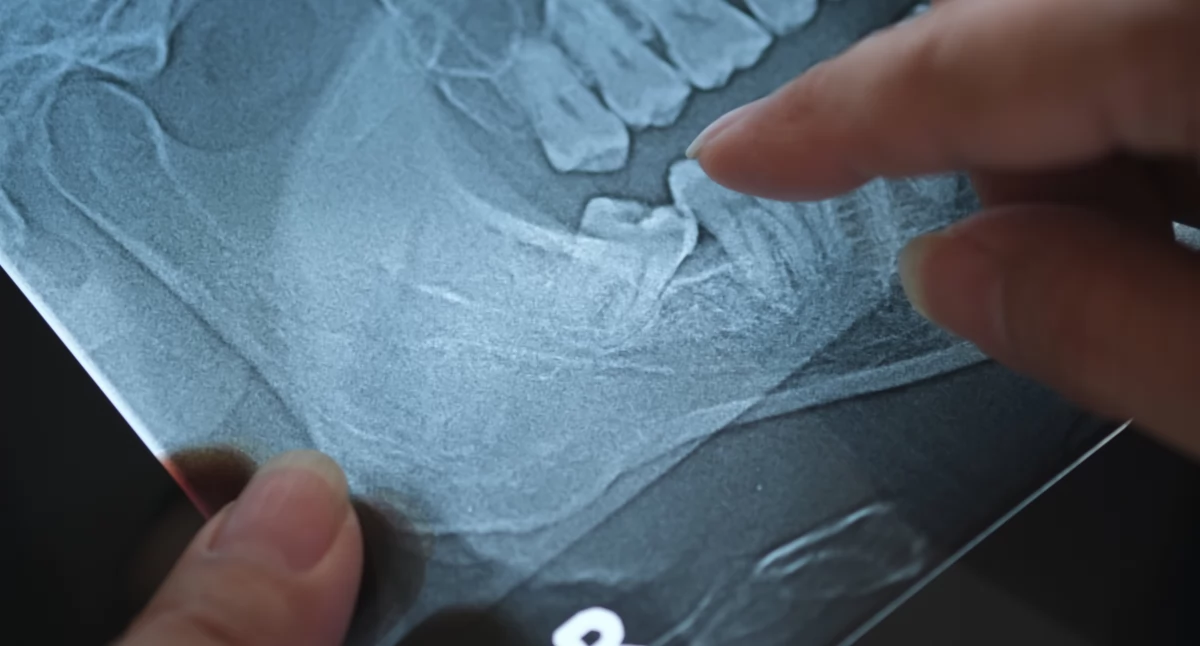

Wśród narzędzi diagnostycznych znajdują się między innymi pantomograf, czyli zdjęcie całego uzębienia oraz tomografia komputerowa pozwalająca na uzyskanie trójwymiarowego obrazu struktur anatomicznych jamy ustnej. Oba badania znacząco podnoszą jakość leczenia i komfort pacjenta.

Pantomografia, czyli panoramiczne zdjęcie zębów, pozwala na szybkie i nieinwazyjne uzyskanie pełnego obrazu uzębienia – od trzonowców aż po stawy skroniowo-żuchwowe. To podstawowe badanie wykorzystywane w wielu przypadkach, między innymi takich jak:

ocena ogólnego stanu zdrowia jamy ustnej, wykrycie próchnicy, weryfikacja korzeni zębowych,

planowanie ekstrakcji zębów, w tym tzw. ósemek, weryfikacja pozycji korzeni zębowych względem innych struktur jamy ustnej,

Tomografia komputerowa to badanie, które umożliwia ocenę stanu uzębienia, tkanek miękkich, zatok oraz ułożenia korzeni względem nerwów i kości.

Klinika DenticaNova w Starej Iwicznej oferuje kompleksową diagnostykę z wykorzystaniem zaawansowanych technologii, są to między innymi pantomografia oraz tomografia komputerowa. Pantomografia umożliwia szybkie, panoramiczne zobrazowanie całego uzębienia i znajduje zastosowanie m.in. w ortodoncji, protetyce czy przed ekstrakcją zębów. Tomografia komputerowa pozwala na uzyskanie trójwymiarowego obrazu struktur anatomicznych jamy ustnej, co jest szczególnie istotne w implantologii, endodoncji i chirurgii.